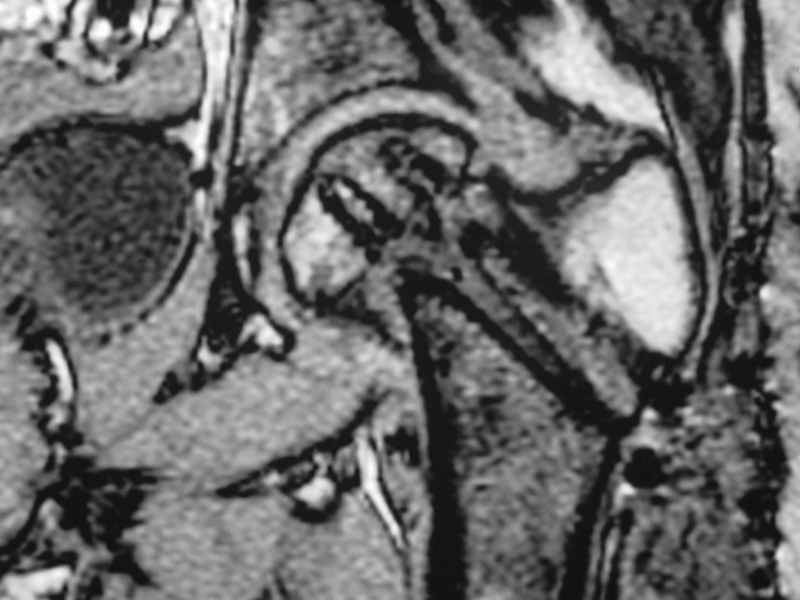

dhs will not correct improper biomechanical environment and may further compromise vascular

integrity consider establish vascular status via mri

and if viable follow with proximal valgus osteotomy

case provided s/p failed fixation